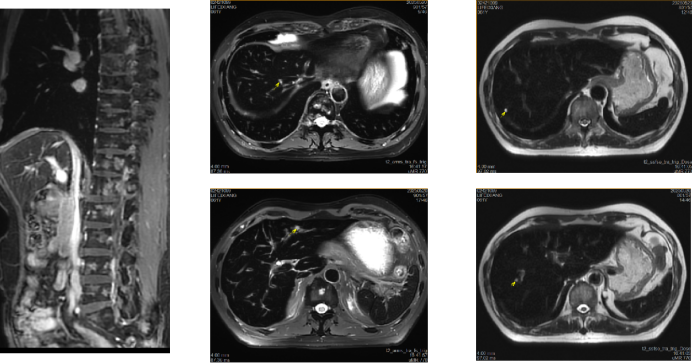

• 肿瘤进展,经多学科会诊,患者化疗副作用明显,要求去化疗治疗,予西妥昔单抗注射液500mg+替雷利珠单抗200mg方案治疗3周期(2024年5月15日、6月5日、6月28日)。

• 疗效评价:PD,新发肺转移,肝转移增多增大。

• 影像学:增强CT(2024年7月18日)

image.png